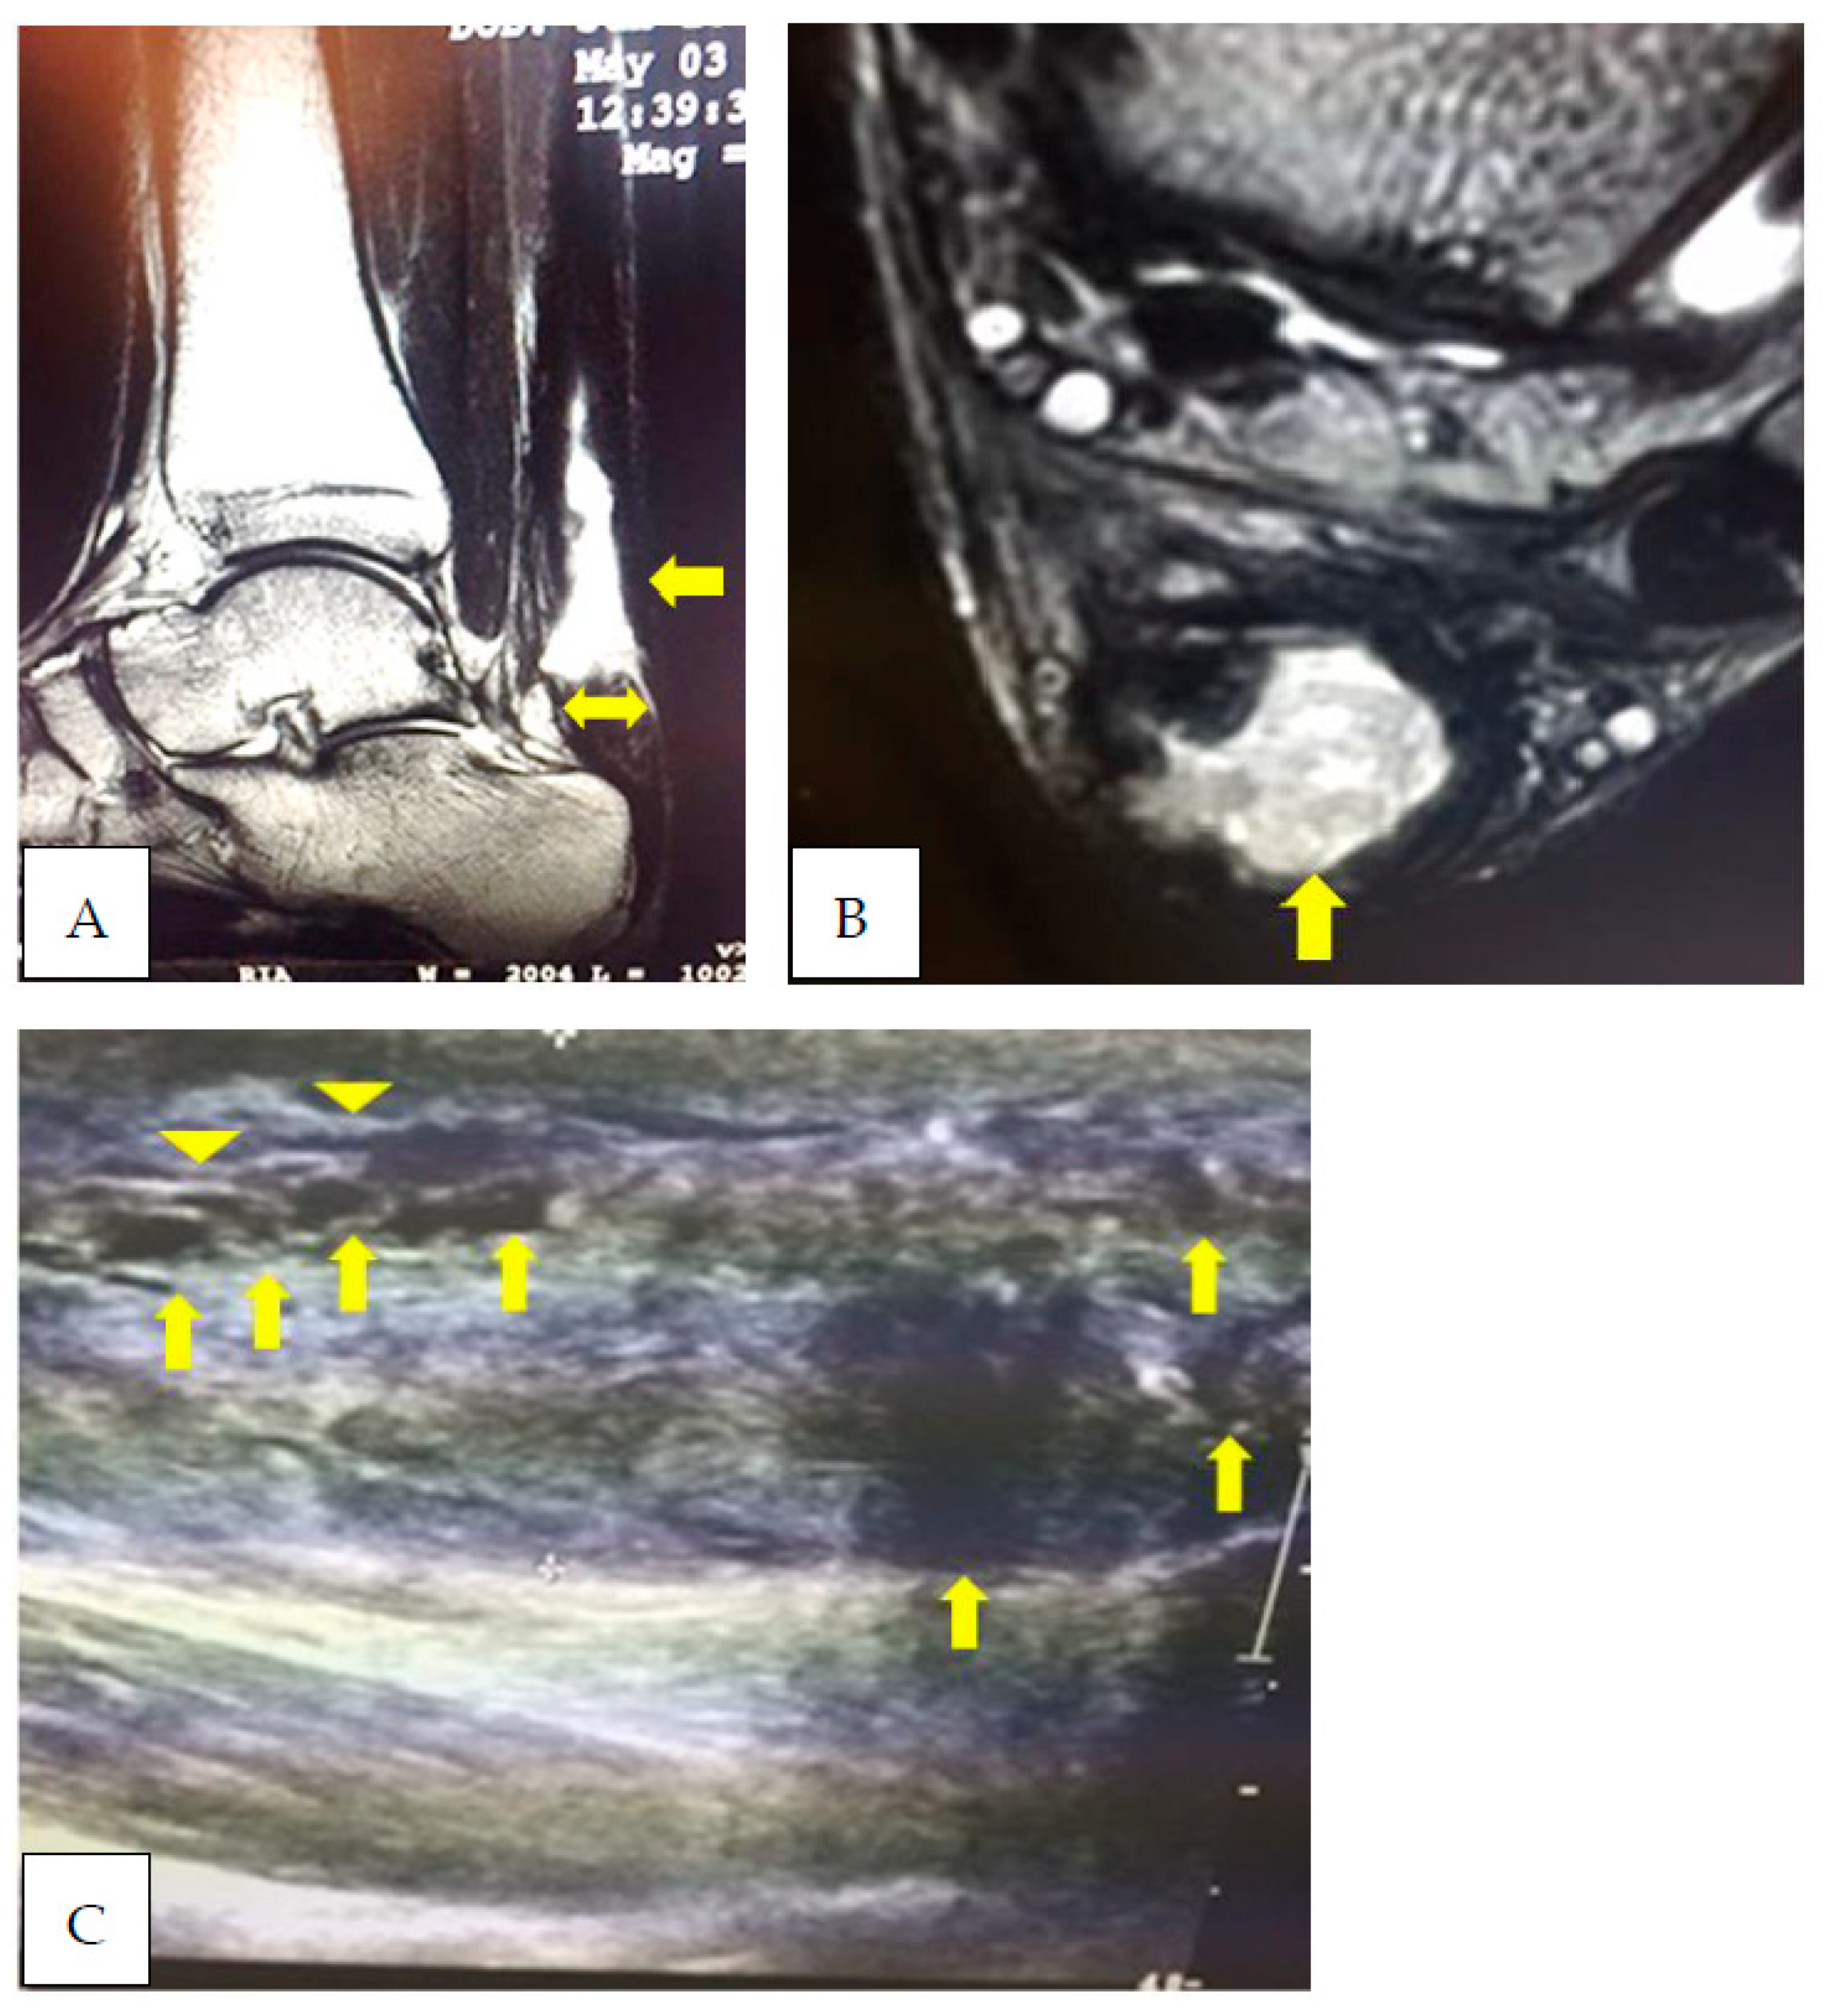

2. Case Presentation